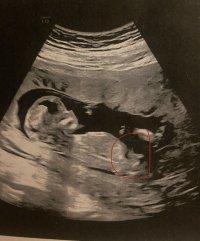

Åå, så kjedelig med dårlige bilder :/.. Jeg har dette også, men her ser man heller ikke stort. Jordmor sa ingenting om hva hun trodde eller noe som helst om kjønnet..Disse bildene var veldig dårlig til å være 14 uker. har du flere fra denne eller tidligere? burde være lett å se kjønn når man er så langt på vei. det på bilde nr 1 er ikke nub, det er en del av benet som har kommet med på bildet. Jeg tror det er jente da det ville vært veldig synlig i uke 14 om det var gutt. Ser og lang hvit strek på flere av bildene som samsvarer med jentenub.